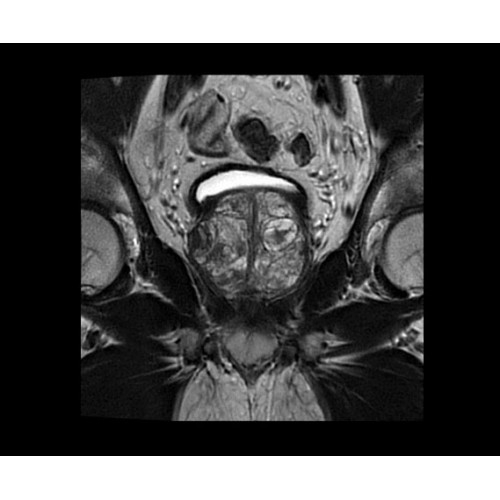

SIGNA PET/MR 3.0T — это гибридная система, в которой совмещаются две принципиально разные технологии — магнитно-резонансную томографию (МРТ) и позитронно-эмиссионную томографию (ПЭТ). Система отличающийся высокой чувствительностью и эффективностью и предназначена для диагностики в области онкологии, неврологии, кардио-васкулярных исследований, исследований воспалительных процессов.

Система SIGNA PET/MR предлагает впечатляющие клинические возможности и открывает доступ к наиболее полным пакетам программных приложений.

Стандартный пакет приложений SIGNA Works позволит вам достичь желаемых результатов в клинической практике благодаря набору высокоэффективных средств визуализации. Программные приложения, входящие в состав данных клинических пакетов, включают широкий спектр контрастов, функции обработки 2D- и 3D-данных, а также возможность коррекции артефактов движения. SIGNA Works предоставляет набор инструментов, необходимых для проведения эффективного клинического исследования.